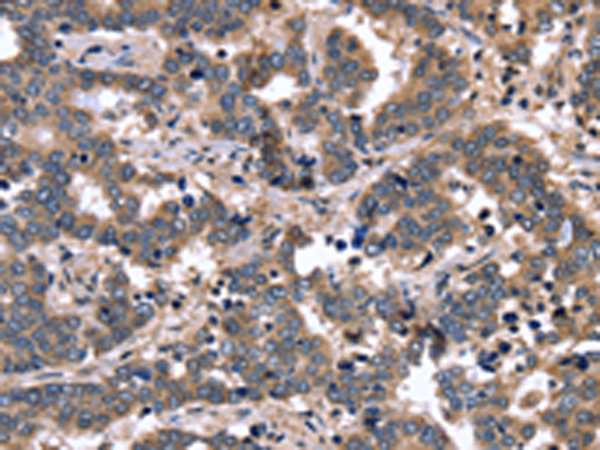

分类: 科研抗体货号: P08330别名: WIT3.0; HSPC123-like应用: IHC反应种属: Human, Mouse, Rat